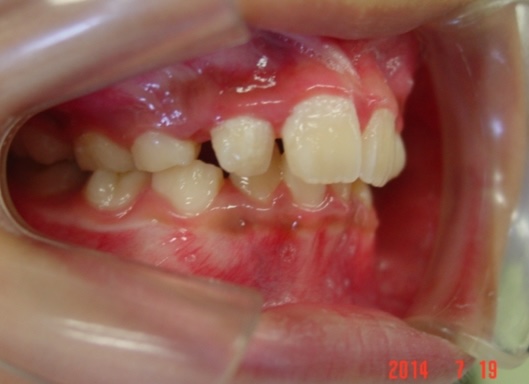

途中経過